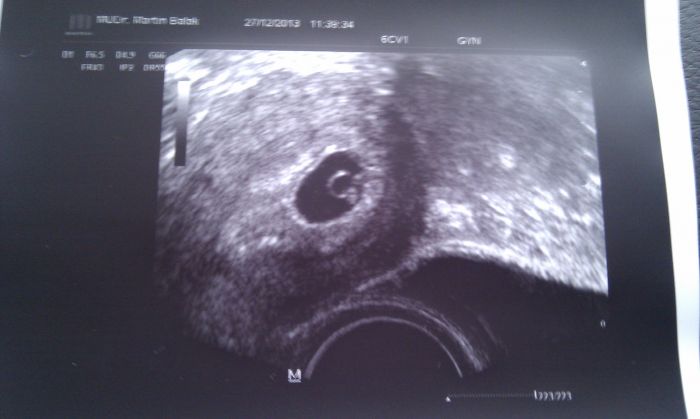

Ahoj holky, dnes koncime 6. týden a tady je fotka z UZ. Srdíčko bije a 10.1. do poradny a uz budu mít i průkazku - to bude 8. týden. Jinak pan dr. rikal, že za těch 14 dní uvidime i jestli tam náhodou nebudou dve. Dvouvajecna vyloucil, ale jednovajecna jeste nevi. A cestou z gyn. jsem si krasne nakoupila saty, s kterymi hezky porosteme :-)